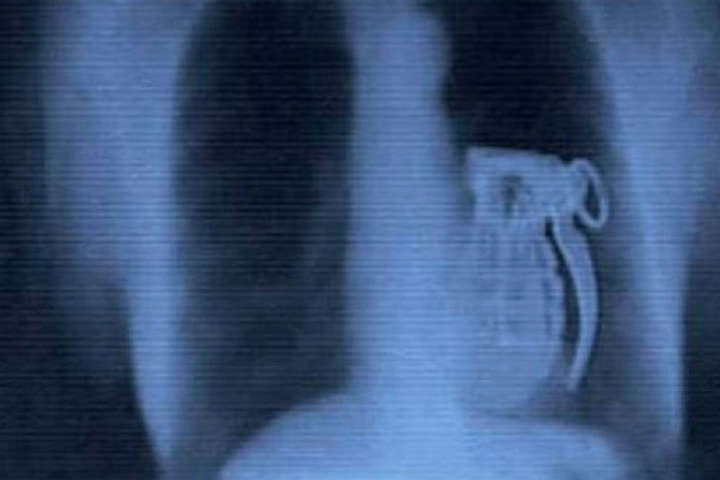

Вот буквально несколько примеров тех вещей, которые были обнаружены в человеческом желудке.